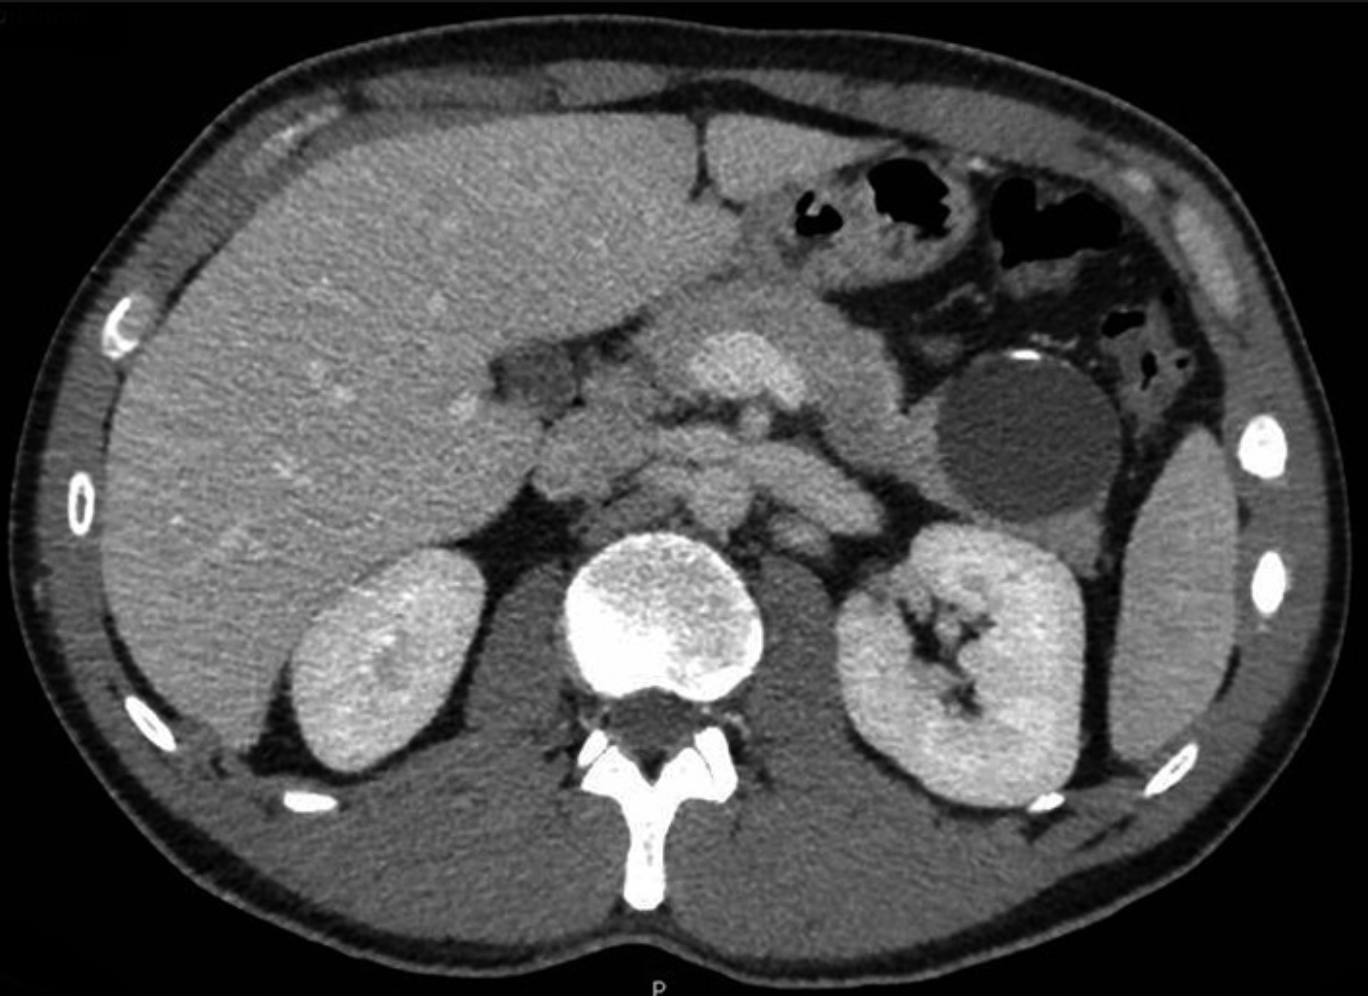

Material y métodos: Presentamos el caso de dicha patología en un varón joven que debutó con dolor en hipocondrio izquierdo y en la pruebas de imagen se evidenció una lesión quística en cola pancreática de 50x45mm, con calcificaciones lineales. Se realizó pancreatectomía distal.